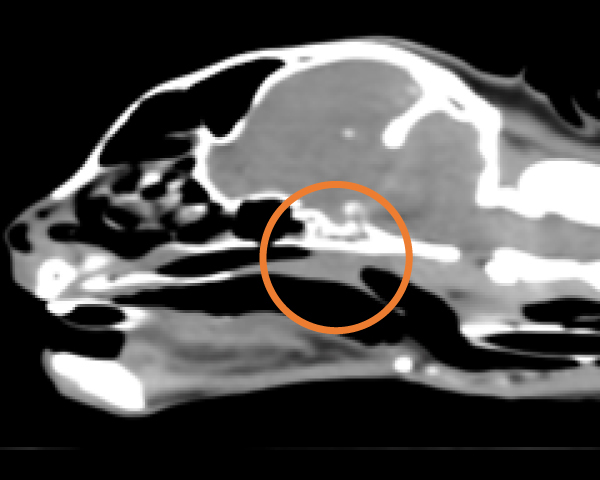

CT検査にて気管の圧迫を確認

内視鏡の位置をCアームで確認し正確に場所の把握が可能

2.8mmと5mmの内視鏡を用いて気管と食道両方の観察・生検が同時に実施可能